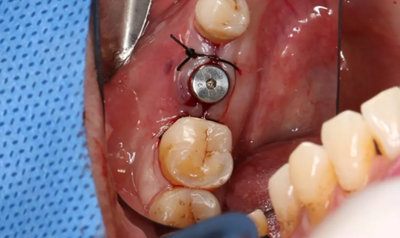

取下攜帶體,旋入封閉螺絲,潛入式愈合。

(攝于2017年4月14日)

組織瓣復(fù)位,常規(guī)間斷縫合。